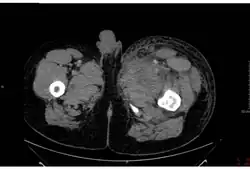

Септическая форма встречается довольно редко. Заболевание начинается остро с озноба и повышения температуры до +39…+40 °C. Наблюдаются выраженные тахикардия, одышка, тахипноэ, боли в груди и кашель с выделением пенистой кровянистой мокроты. Определяются признаки пневмонии и плеврального выпота. При развитии инфекционно-токсического шока возникает геморрагический отёк лёгких. В крови и мокроте обнаруживают большое количество сибиреязвенных бактерий. У части больных появляются боли в животе, присоединяются тошнота, кровавая рвота, жидкий кровянистый стул. В последующем развивается парез кишечника, возможен перитонит. Обнаруживаются симптомы менингоэнцефалита. Инфекционно-токсический шок, отёк и набухание головного мозга, желудочно-кишечное кровотечение и перитонит могут явиться причиной летального исхода уже в первые дни заболевания.